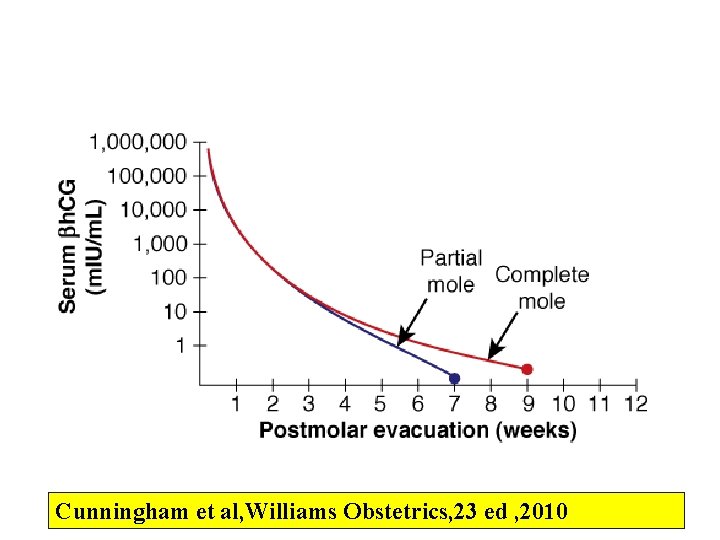

Cunningham et al, Williams Obstetrics, 23 ed , 2010